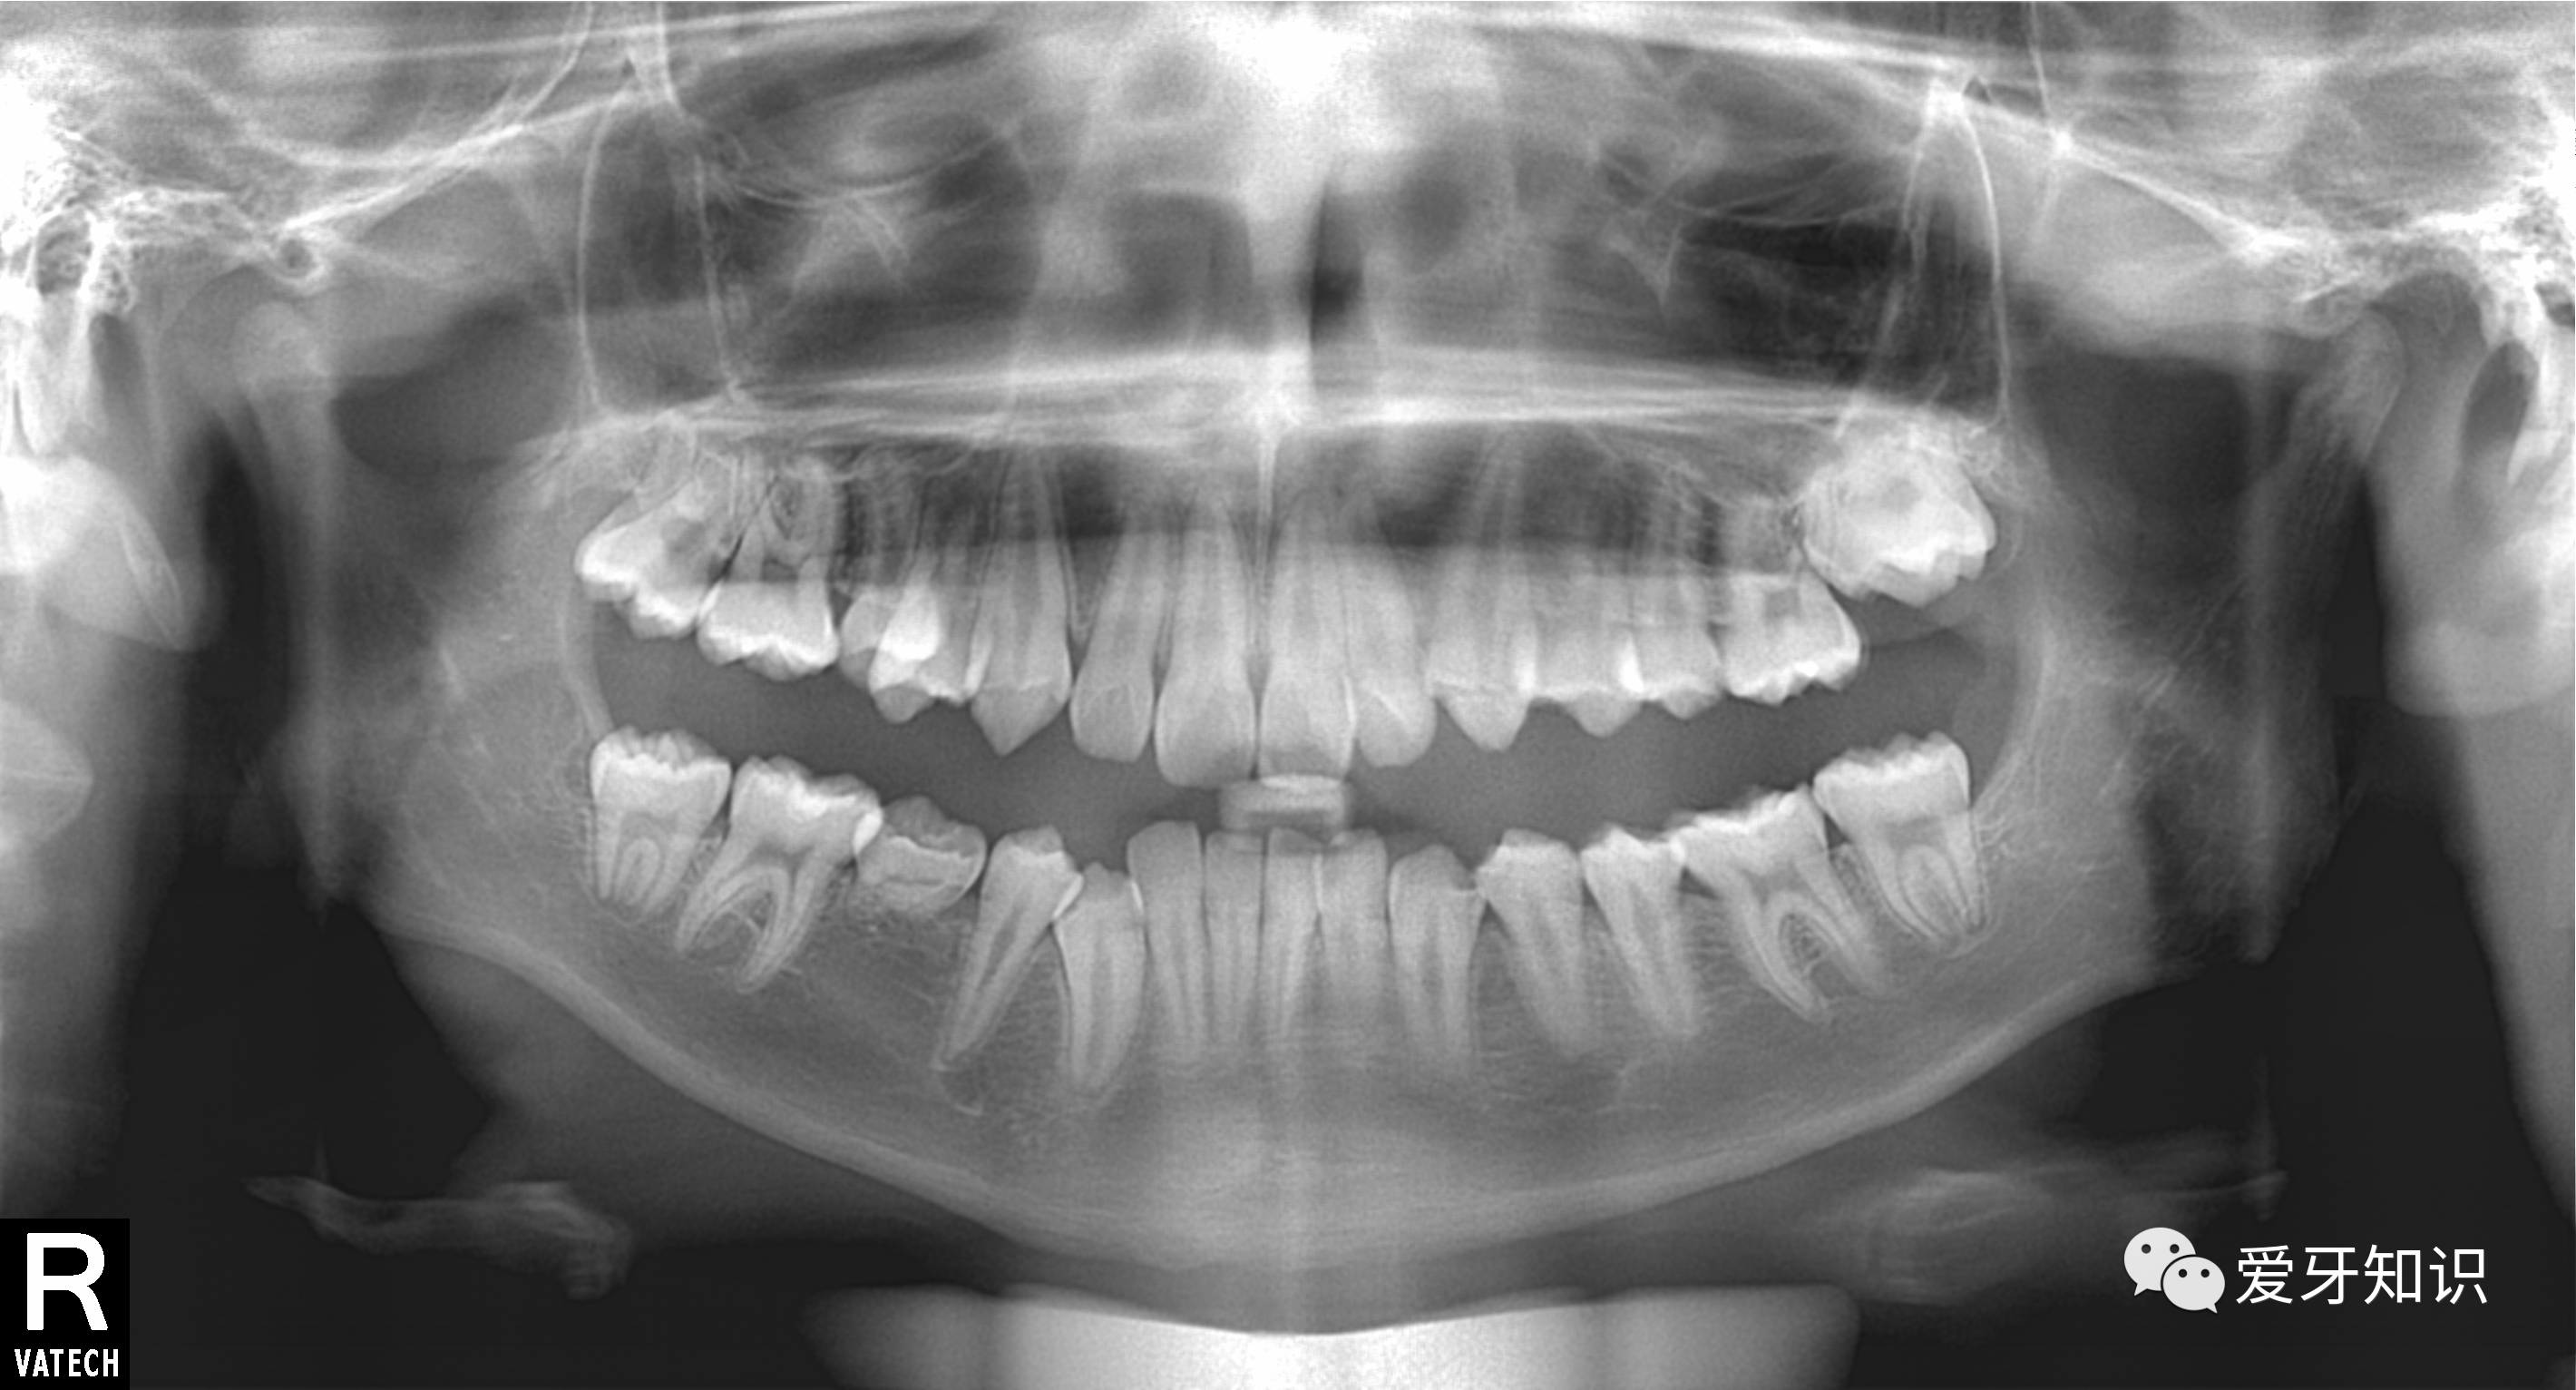

拿这个患者举例吧,口内可见龋坏已经很深了。牙医只是凡人,没有透视眼,看不穿龋坏到底烂到什么程度,是否影响到牙髓及牙齿根尖周围的牙槽骨。我们还是需要配合x光影像学检查来辅助诊断的。